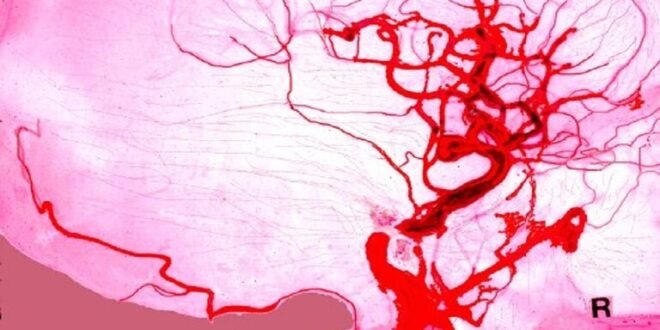

وجاء في منشور لمجلة “العلوم في سيبيريا” التابعة للأكاديمية:”لأول مرة في روسيا، تمكن العلماء من تطوير مواد بوليميرية جديدة يمكن استعمالها في ترميم جدران الأوعية الدموية لمنع تمزقها، الأمر الذي سيقلل من أخطار النزيف في الجسم وأخطار الجلطات والسكتات الدماغية”.